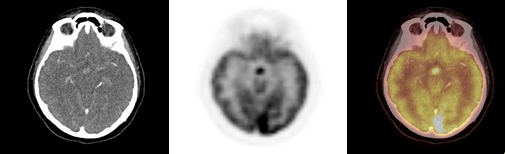

Se obtuvo un estudio PET-CT de cuerpo entero 50 minutos después de la administración IV de 7,8 mCi de 18F-FDG; el componente CT se realizó con medio de contraste yodado (equipo Siemens mCT). El estudio demostró lesiones osteolíticas hipermetabólicas en la cabeza humeral derecha, cavidad glenoidea y partes blandas adyacentes con valor de captación estandarizado (SUVmax) = 9,2. También mostró múltiples lesiones osteolíticas e hipermetabólicas vertebrales y costales con masa de partes blandas hipermetabólica que infiltra la musculatura dorso-lumbar y femoral. Se observó aumento del metabolismo en el plano cutáneo de axila izquierda y vulva, en correspondencia con lesiones ulceradas, así como también un nódulo hipofisario de 14 mm, hipermetabólico, con SUVmax = 22,5 (figs. 1,2 y 3 A). Los pulmones, mediastino, hígado, bazo, glándulas suprarrenales y páncreas no presentaron alteraciones del metabolismo ni tampoco se identificaron adenopatías hipercaptantes.

Un 18FDG PET-CT de control post-terapia (figs. 1,2 y3 B) mostró significativa disminución metabólica de la lesión hipofisaria, del componente de partes blandas en hombro derecho y de las lesiones en columna, con persistencia sin cambios de las lesiones osteolíticas en TAC. Dada la respuesta parcial a la terapia, se inicia segundo curso de vinblastina semanal 6 mg/m2 por 6 semanas y prednisona 40 mg/m2 por 3 días a la semana.